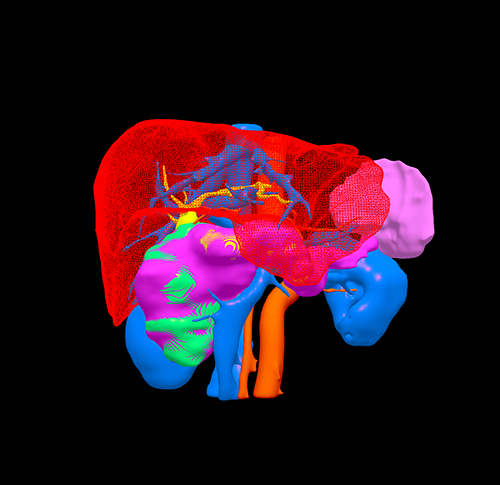

三维重建

胰头囊腺瘤---胰十二指肠切除